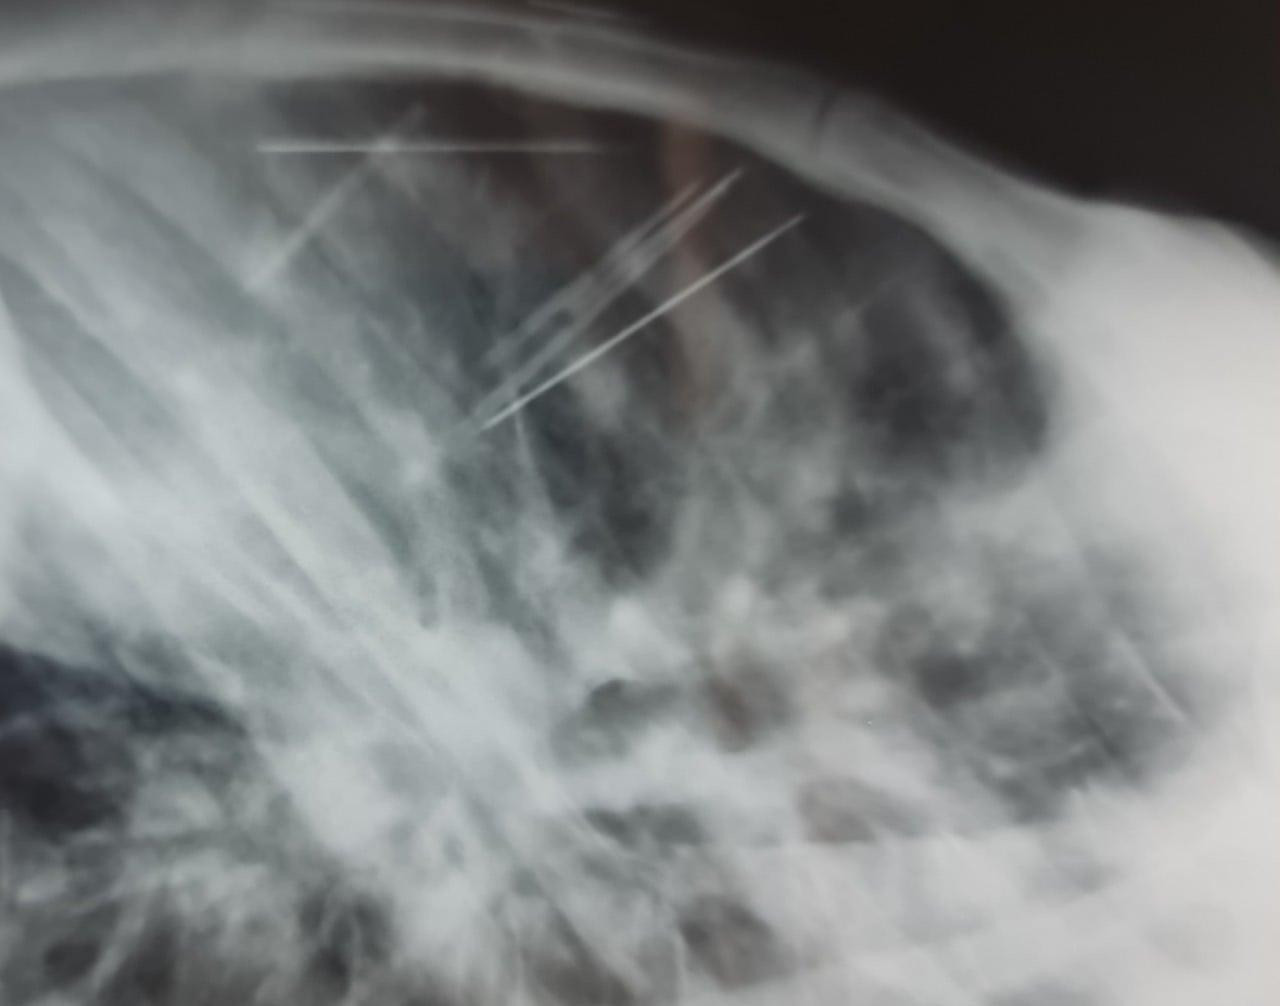

Tiếp nhận bệnh nhân, các bác sĩ tiến hành chụp X-Quang và CT-Scan lồng ngực thì bất ngờ phát hiện có 7 dị vật hình dạng như chiếc kim khâu dài khoảng 4cm nằm ở trung thất và khoang màng phổi trái của bệnh nhân, kèm theo đó là tràn dịch màng tim lượng vừa.

Quá trình mổ, ekip ghi nhận 1 chiếc kim đâm vào nhĩ trái, 3 chiếc đâm vào quai động mạch chủ, 1 chiếc đâm thủng thùy trên phổi trái, 1 chiếc trong khoang màng phổi trái và 1 chiếc bị gãy đôi nằm trong cơ thành ngực.